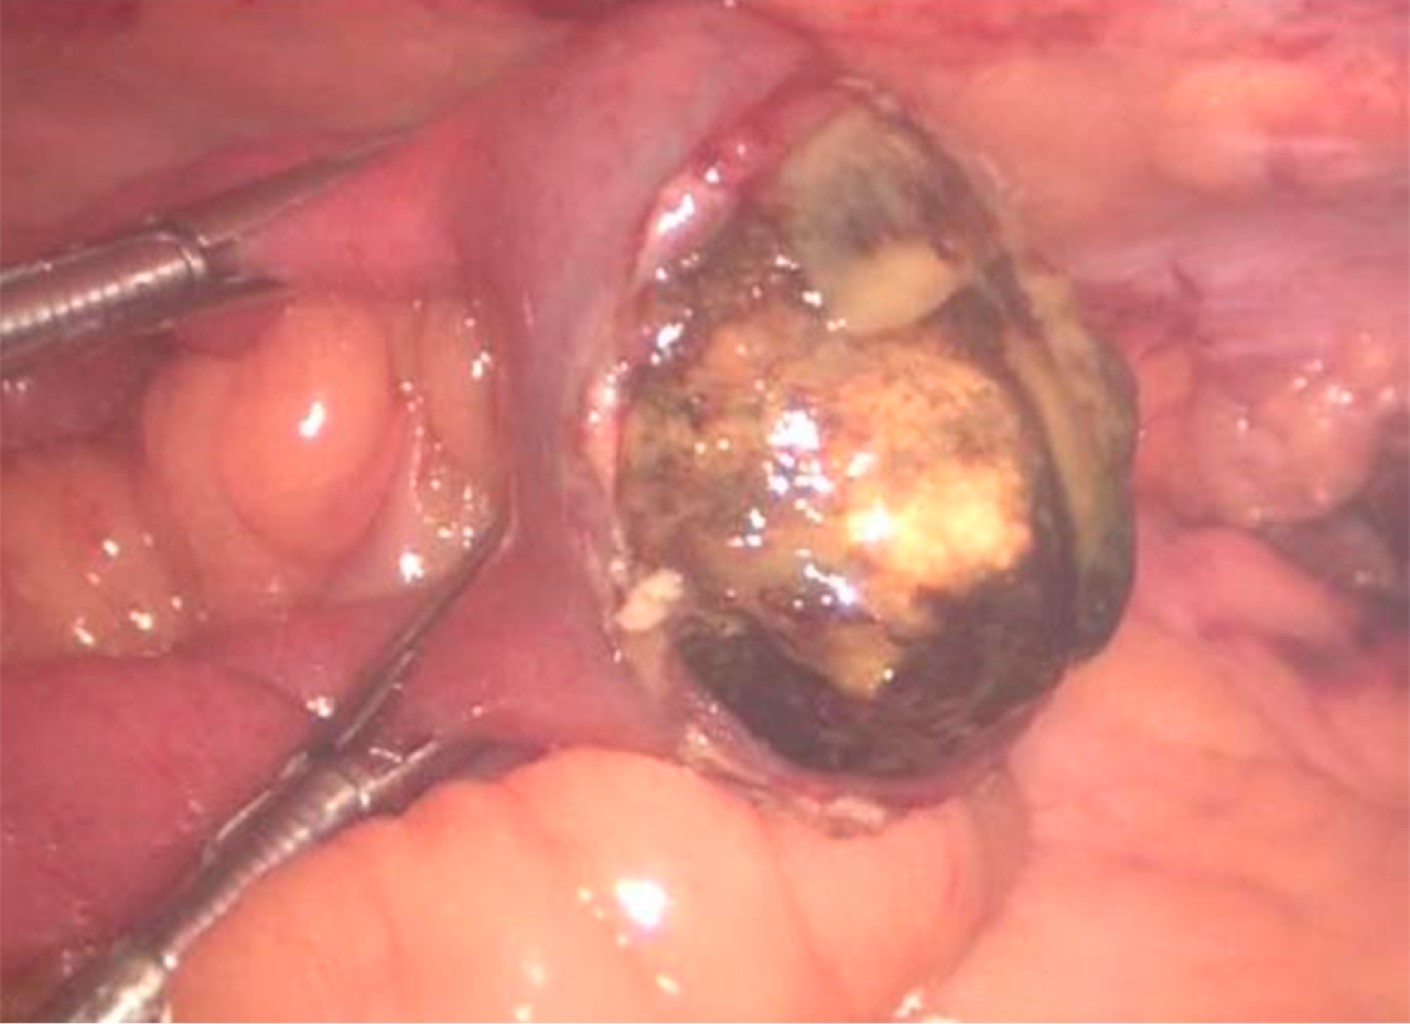

Introduction: Gallstone ileus is a mechanical obstruction of the gastrointestinal tract caused by the impaction of one or more gallbladder stones inside the intestinal lumen through a bilioenteric-fistula. Clinical case: A 59-year-old woman with multiple comorbidities, who went to the emergency room for intestinal obstruction, pneumobilea, and bowel distention is identified by image, so it was decided to enter the operating room for a probable biliary ileus and perform diagnostic laparoscopy, finding a 3.5 cm diameter lithium located in the terminal ileum. Conclusion: Gallstone ileus is a rare complication of cholelithiasis. The treatment integrates rehydration and a surgical approach to correct the cause of intestinal obstruction.

Figure 1